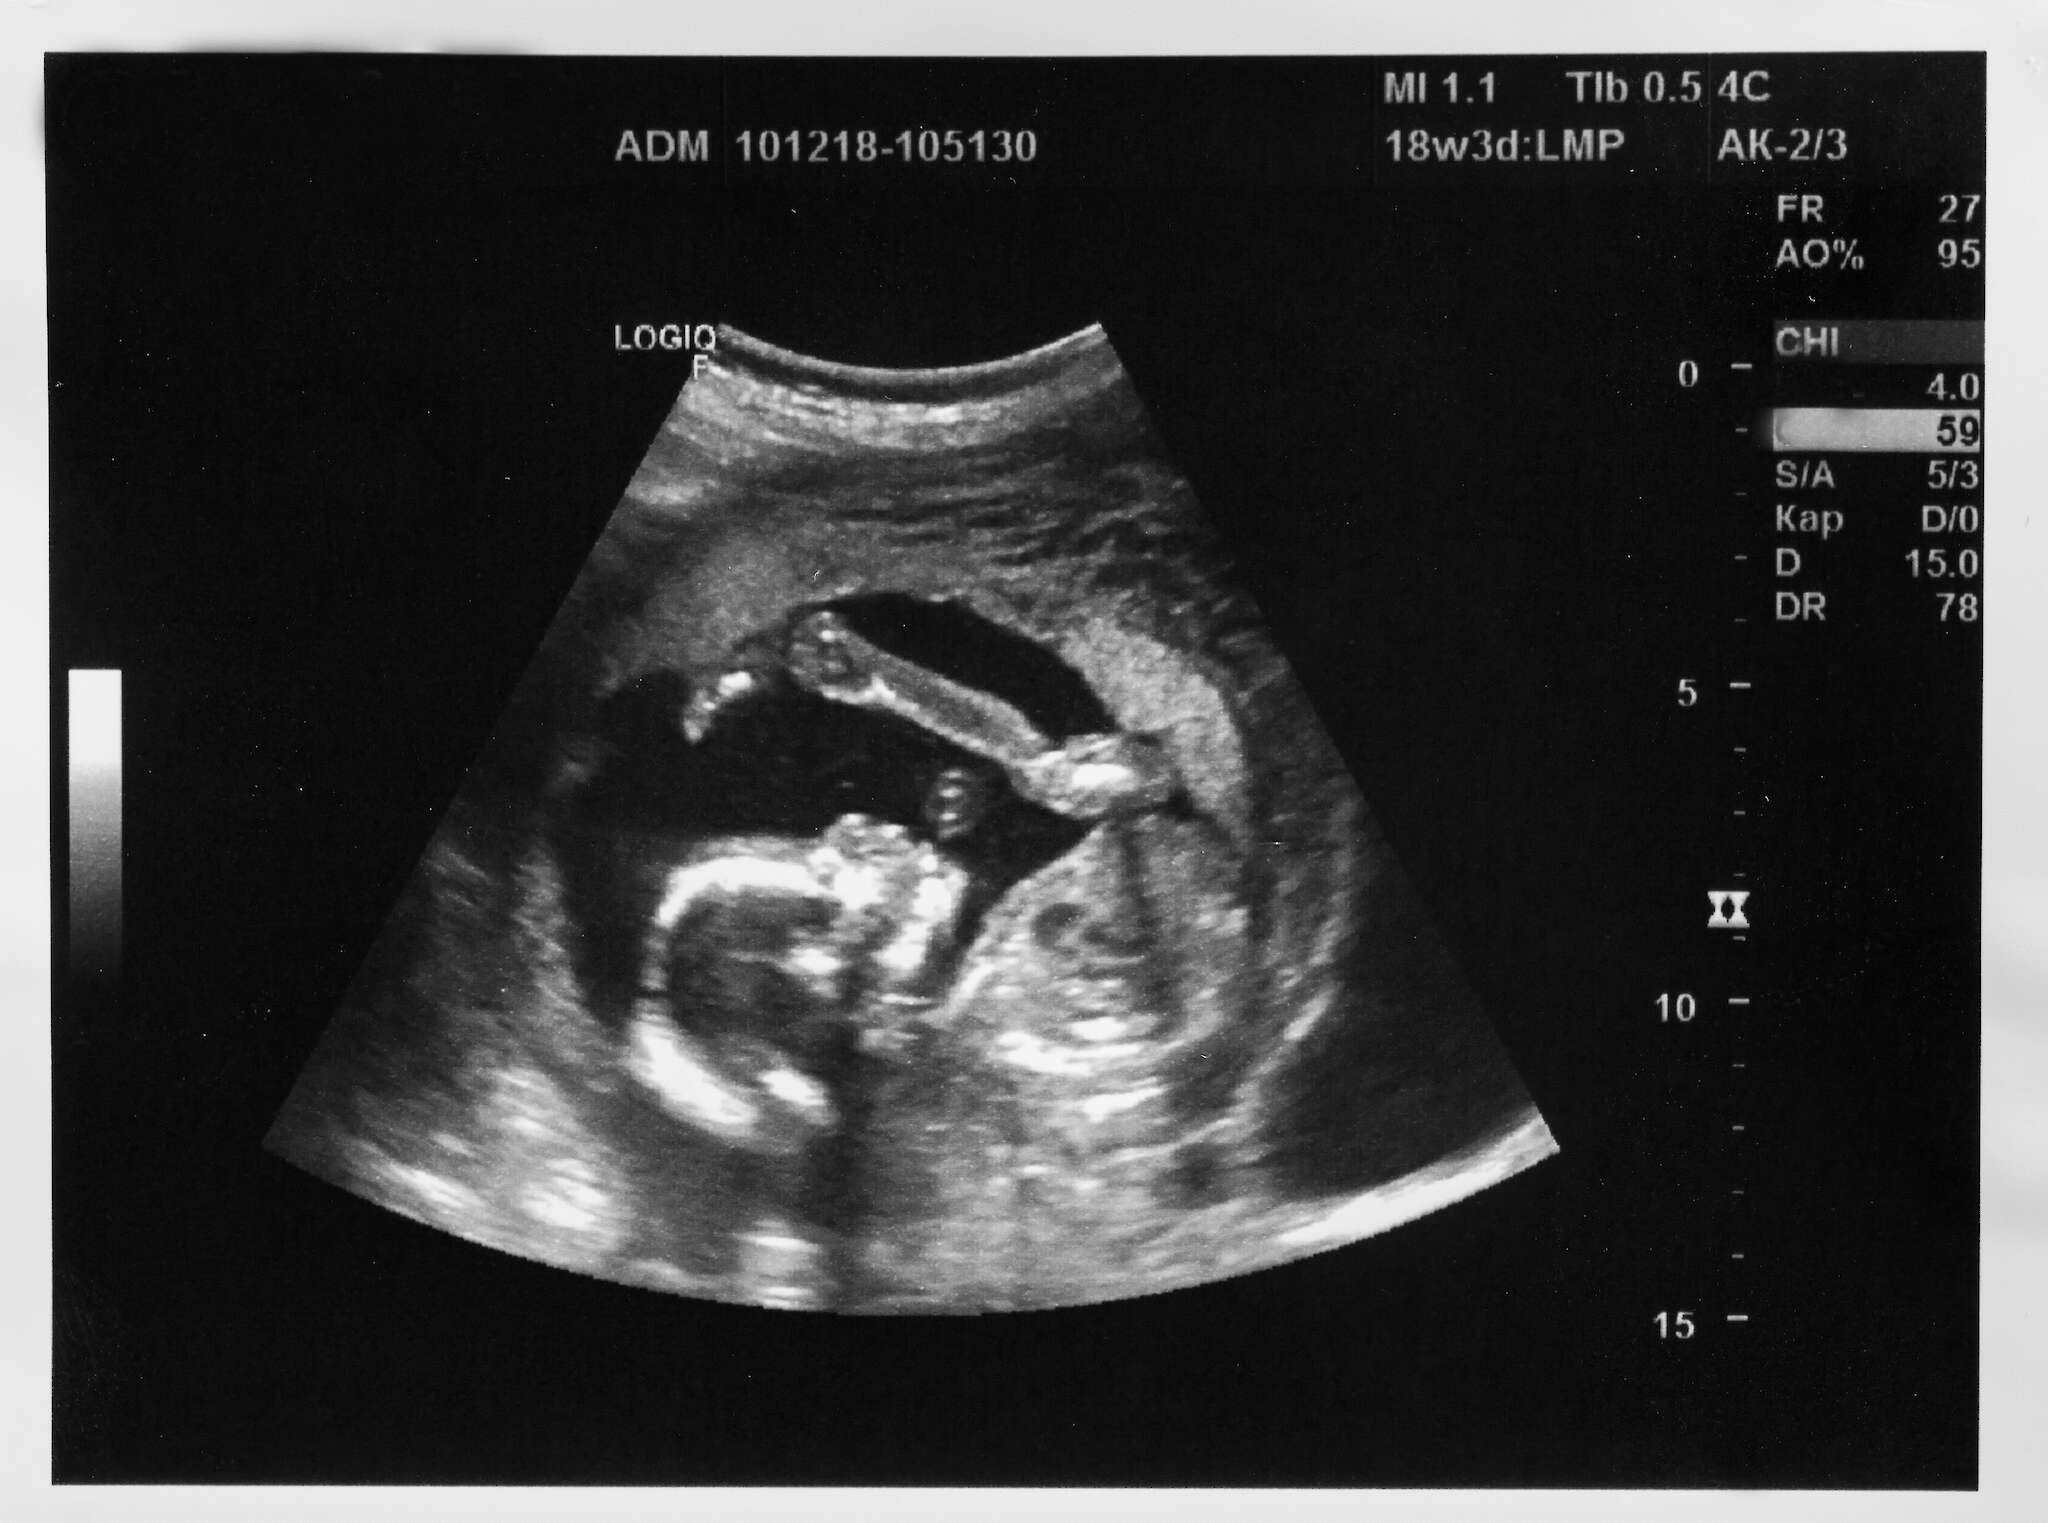

Tutkimuksiin kuuluvat keski- ja loppuraskauden ultraääni, sikiön yleisvoinnin kuvantaminen sekä kasvun mittaaminen.

Listoilta löytyvät myös sikiön liikelaskenta, lapsiveden määrän arviointi ja jopa synnytystapa-arvio.

Tuloksista tehdään johtopäätöksiä, asetetaan diagnooseja ja annetaan suosituksia. On annettu jopa raskauteen liittymättömiä gynekologisia diagnooseja.